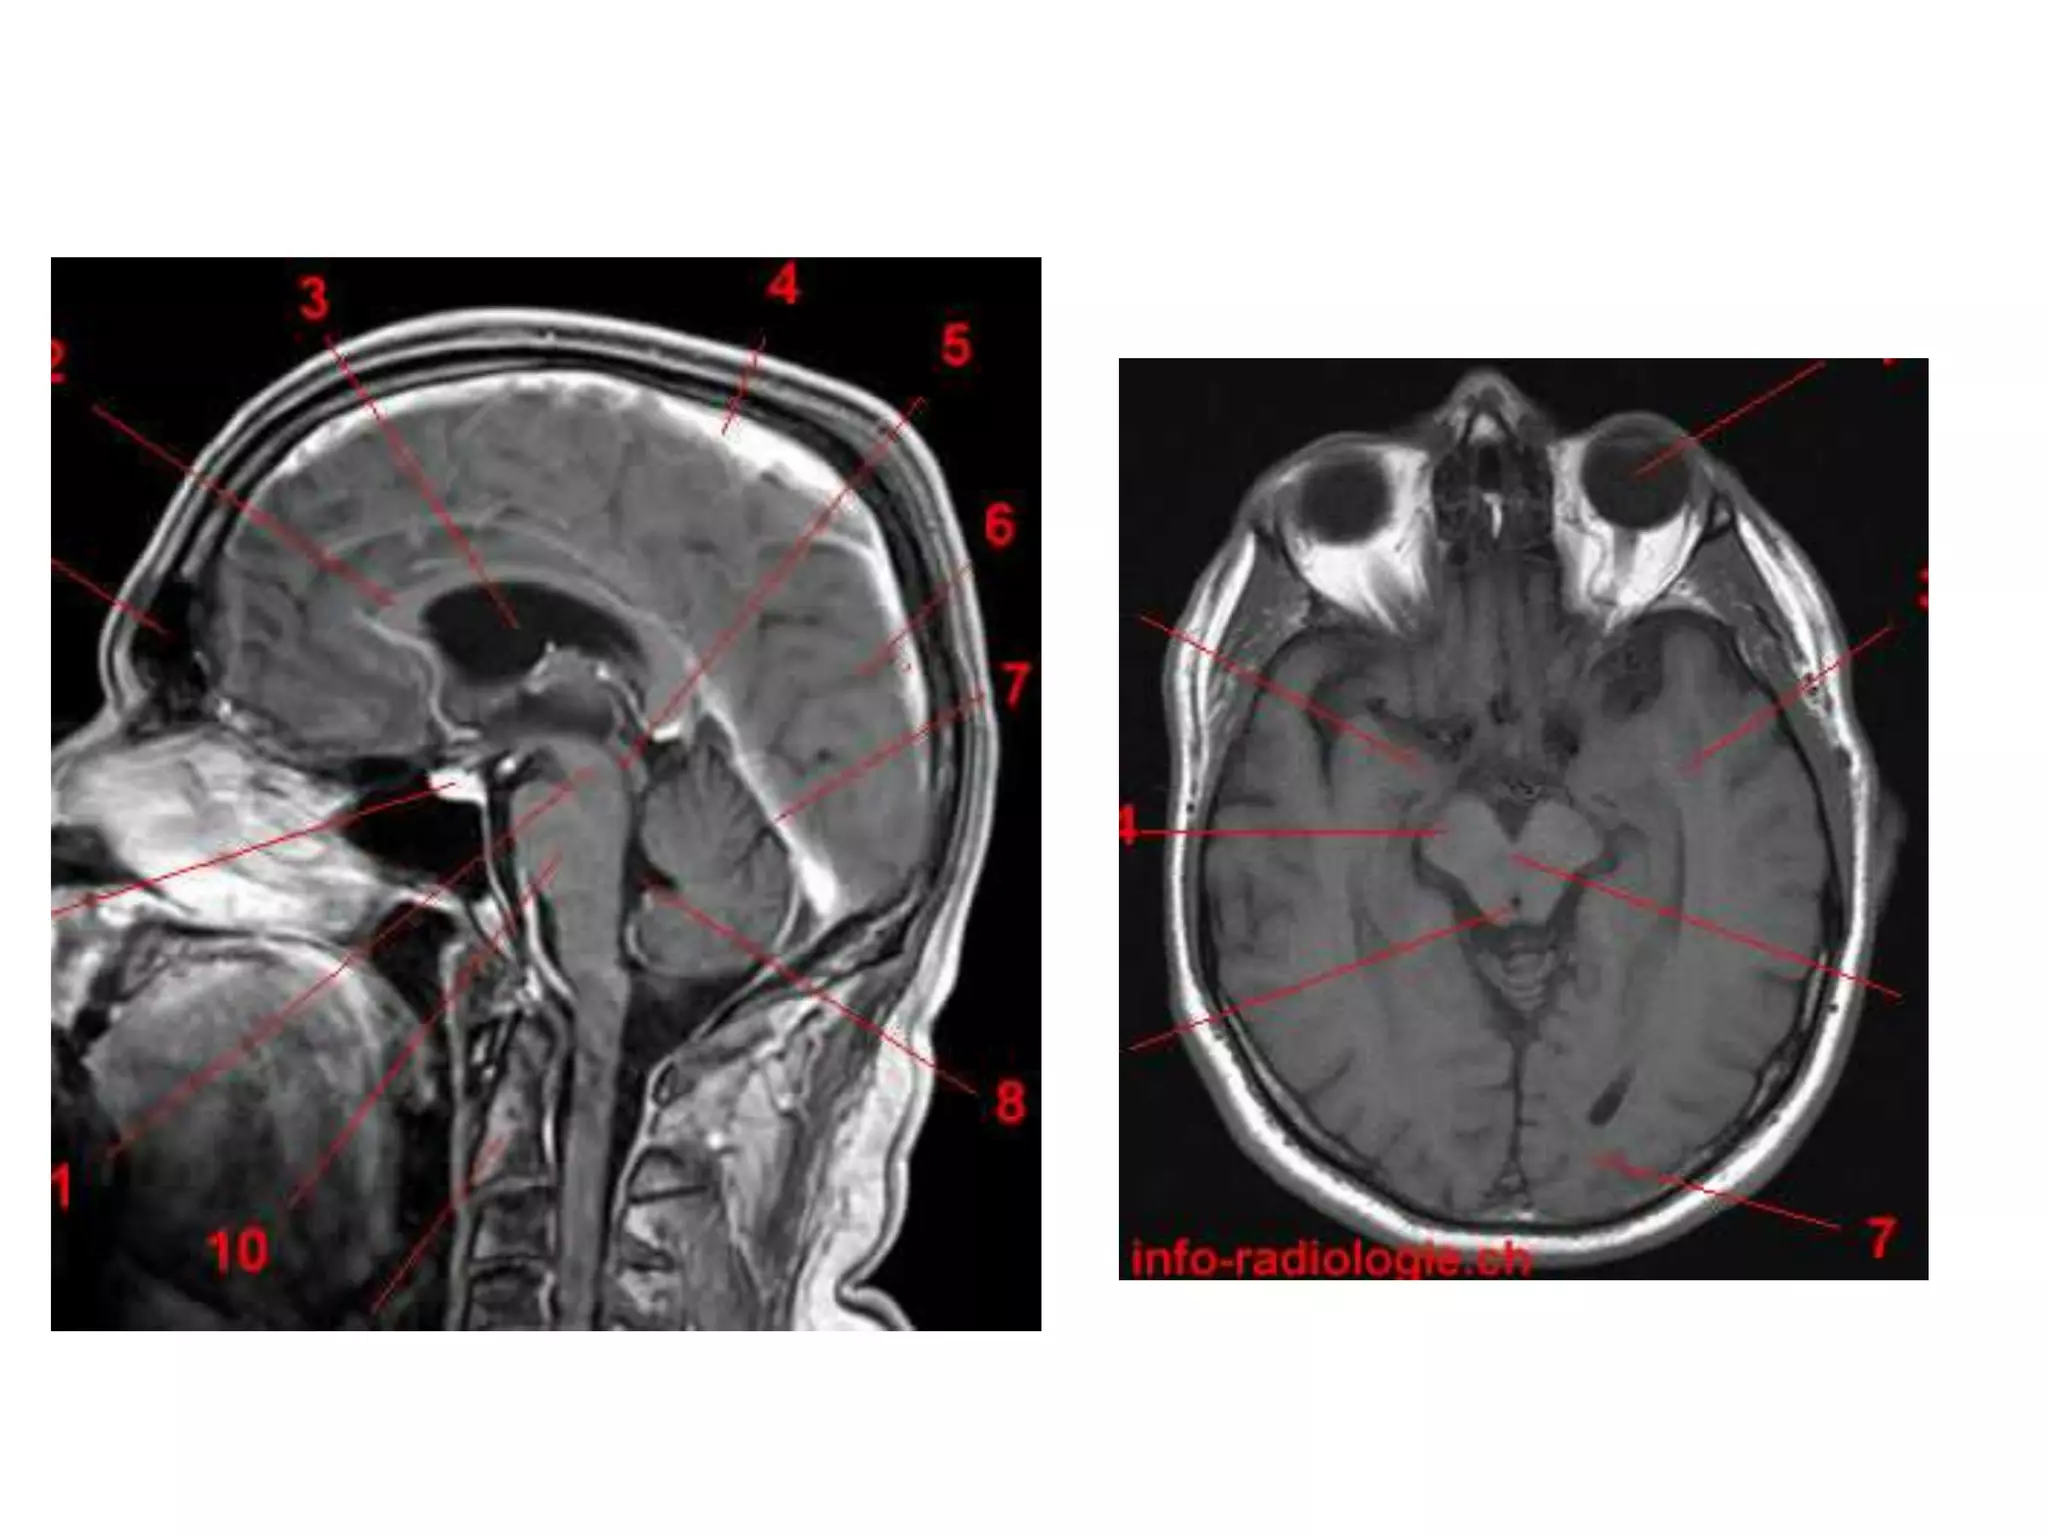

• Anatomy of cerebral hemispheres and mid brain – T1 W

MRI.

• Internal grey - white matter areas – T2 W MRI.

• Saggital and Coronal T1 weighted MRI – accurate

assessment of ventricles and C. callosum

• Mid Saggital section – for shape and configuration

of Aqueduct of Sylvius.

• Radiology –

Axial MRI / CT - narrow cleft

Saggital MRI – elongated and complex curved shape

with upward, backward & downward arc.

Radiology

• Axial MRI / CT – ‘kidney bean’ turned on its side.

• Saggital MRI - mid point of line drawn b/w T. sella

and trocula should intersect middle of 4th

ventricle.

• Coronal MRI – elongated rhomboid shape

CISTERNS

• Where brain and skull are not closely

apposed, arachnoid and pia separate – and form

cisterns .

• Mainly present at base of brain, around brain stem and

free edge of tentorium.